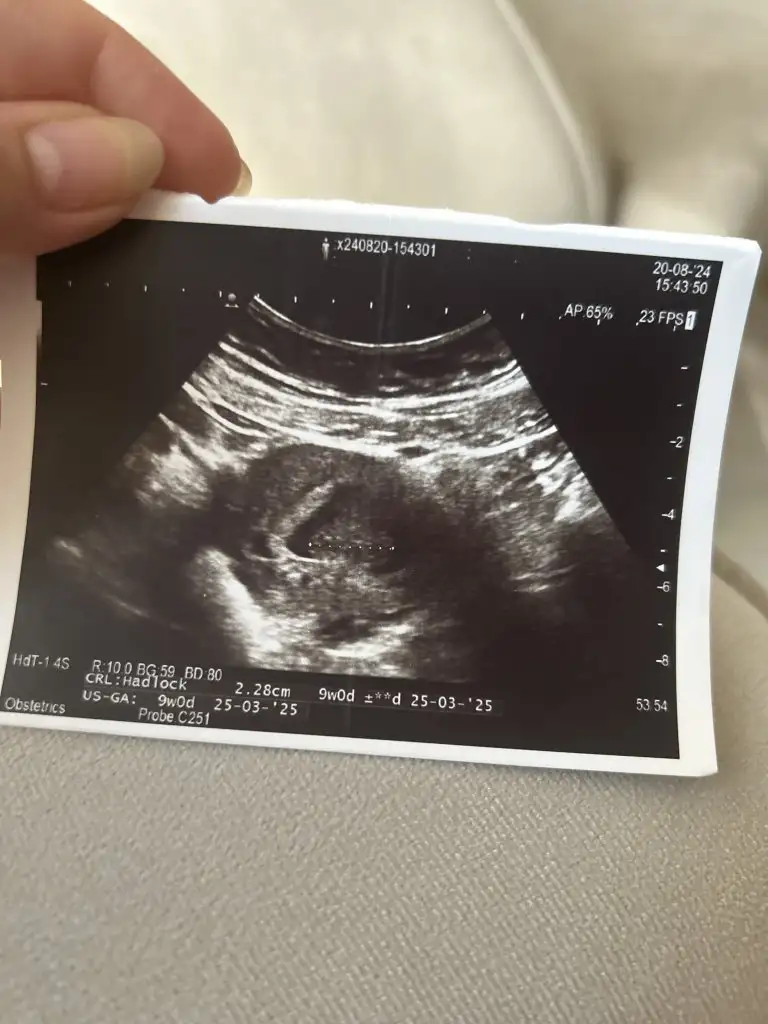

Oy maşallah subhanallahMerhaba benimkini de tahmin edebilir misiniz acaba :)Eki Görüntüle 3471936

Bu da benimki teyzesi, sen bir tahminde bulunur musunMerhaba benimkini de tahmin edebilir misiniz acaba :)

Bence erkek olacak neden bilmiyorum bende hamileyim öyle hissettim bide bana tahminde bulunur musunuz 13 haftalık olduBu da benimki teyzesi, sen bir tahminde bulunur musun

Gerçekten mi insallah gönlümüzden geçen erkek nasip bakalımMaşallah lokumaiçimden erkek geçti çünkü aynı benim oğlumun ultrason görüntülerine bakıyor gibi hissettim. Çok benziyor, arkadan olan görüntüsü hele ki